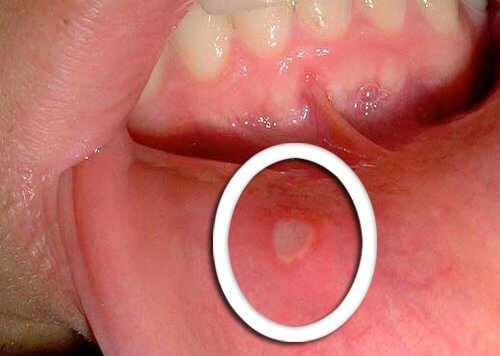

嘴破

• 口咽癌的最早症狀是不會癒合的小潰瘍。

• 在舌頭、牙齦或嘴唇上出現紅色或白色的傷口是典型症狀。

• 請注意任何沒有在幾天內改善的不尋常變化,並讓你的醫生知曉。